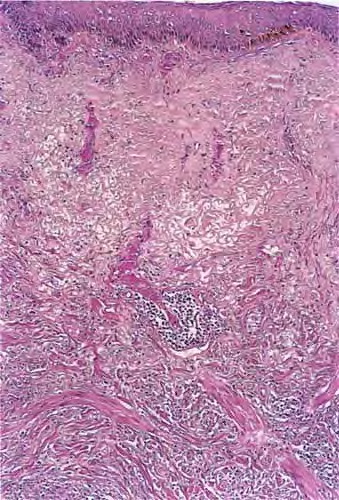

Desmoplastic melanoma = الميلانوم المكون للالتصاقات